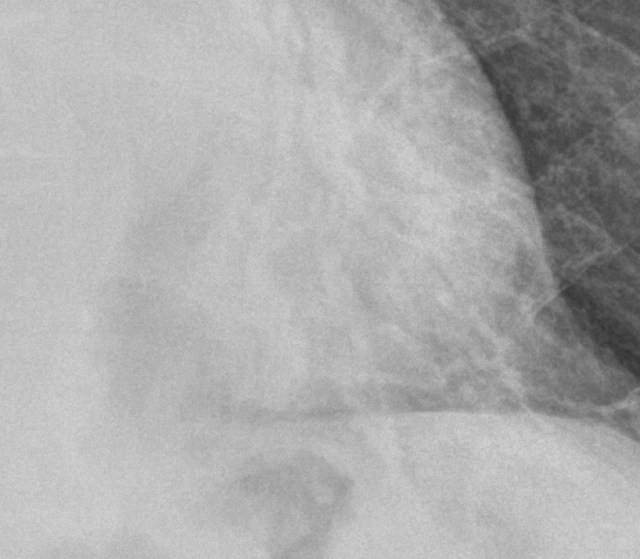

이 환자의 옆에서 가슴을 촬영한 영상입니다. 이 사진만 봐서는 애매할 수 있겠지만, 이런 측면영상을 많이 본 의사라면 심장 뒤쪽의 폐가 많이 하얗다는 걸 눈치챌 수 있습니다. 하얗다, 내지 뿌옇다는 것의 기준이 애매하기 때문에 사실, 더 위쪽의 영상이 훨씬 병변을 명확하게 잘 보여주고 있지만, 실루엣징후에 대한 이해가 부족한 의사라면 오히려 이렇게 옆에서 촬영한 영상에서 폐렴의 가능성을 더 쉽게 찾을 수 있습니다. 어쨋던, 임상정보에 기대어 이렇게 추가적인 조치를 제대로 할 수 있는 단계라고 한다면, 초보의사는 아닙니다. 완벽하진 않지만 실수없이 정확한 경로를 밟아서 환자에게 도움이 되는 조치를 취할 수 있는 “중수”라고 말할 수 있으며, 현장에서 진료에 임할 수 있는 상태입니다.